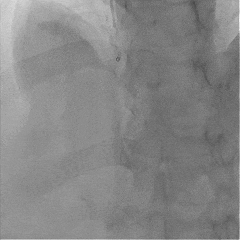

冠脉造影提示:左主干未见狭窄;左前降支近段局限性狭窄50%,中段最重狭窄40%,TIMI血流3级;回旋支无狭窄;右冠状动脉近中段可见弥漫性中度钙化,TIMI血流3级,最重狭窄70%;右冠状动脉远段TIMI血流0级,最重狭窄100%。

根据心电图及临床症状,结合冠脉造影结果考虑右冠脉为罪犯血管,决定开通右冠脉闭塞病变。

介入治疗过程:将导丝通过右冠脉中远段闭塞病变送至血管远端,送入血栓抽吸导管抽吸出红色血栓,使用球囊对病变处进行预扩张,造影示闭塞病变开通,OCT观察闭塞病变处可见红色血栓及斑块破裂,最小面积3.35mm2。后成功于病变处放置3.0×18mm药物洗脱支架一枚,造影示支架定位良好,未见明显夹层,OCT观察支架贴壁良好,支架内无血栓及夹层影,远端血流TIMI 3级,最小管腔面积5.59mm2。